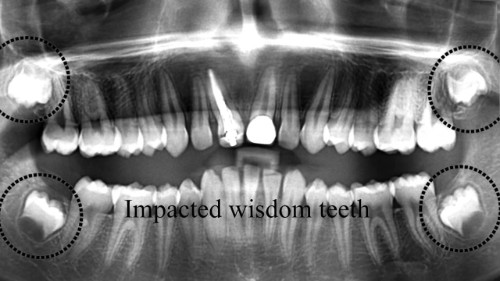

After Extraction of Wisdom Teeth